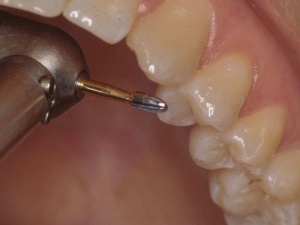

Mastering Occlusal EquilibrationGordon J. Christensen, DDS, MSD, PhD & Valinda Johnston, BS, CDA We are seeing unprecedented levels of cracked natural teeth, TMD, and tooth loss because of occlusal malfunction. Rigid, wear-resi...... |

Occlusal Splints Are Essential!Gordon J. Christensen, DDS, MSD, PhD; Karen Preston, MAEd, RDH, FHEA; & Ric Schwarting, BS Occlusal principles and techniques have become much more essential because of changes in restorative mat...... |

Opening Vertical Dimension of OcclusionOpening Vertical Dimension of Occlusion (and Adjunctive Occlusal Procedures) Gordon J. Christensen, DDS, MSD, PhD Occlusion is one of the most controversial and frustrating areas of dentistry, yet y...... |

Treating Muscular TMD Is SimpleGordon J Christensen, DDS, MSD, PhD You see this condition routinely, but many dentists don’t treat it. Why? About 80% of temporomandibular dysfunction (TMD) is muscular only, without bony involveme...... |